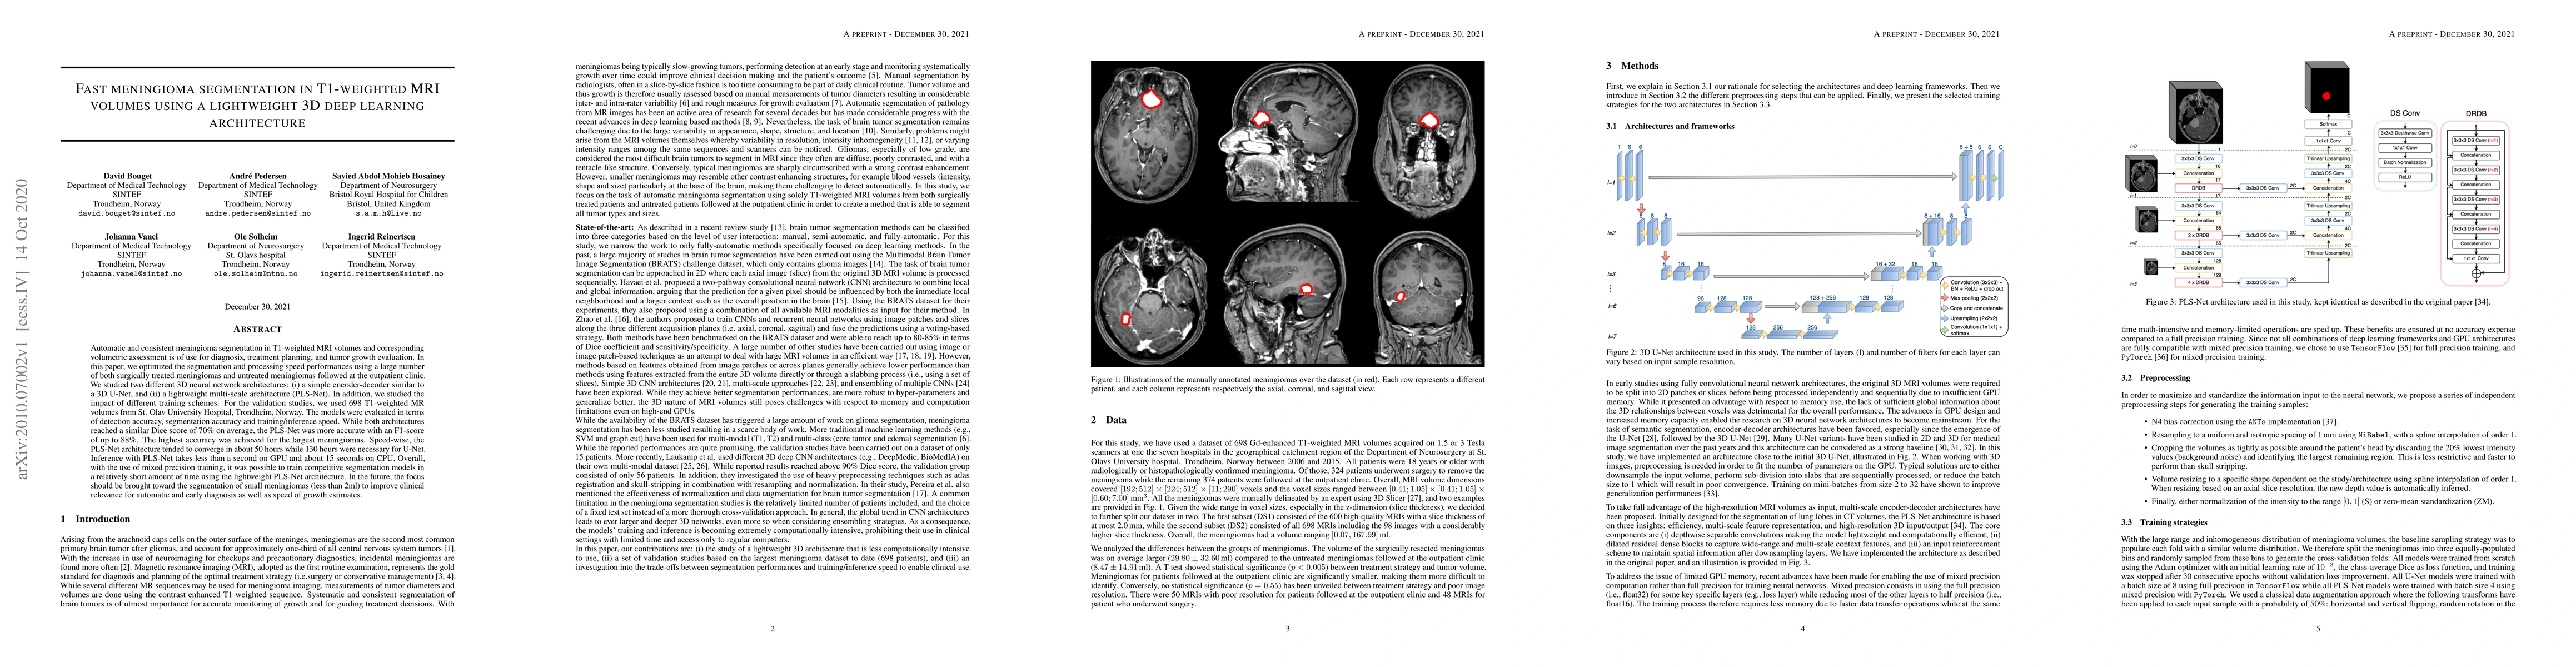

Automatic and consistent meningioma segmentation in T1-weighted MRI volumes and corresponding volumetric assessment is of use for diagnosis, treatment planning, and tumor growth evaluation. In this paper, we optimized the segmentation and processing speed performances using a large number of both surgically treated meningiomas and untreated meningiomas followed at the outpatient clinic. We studied two different 3D neural network architectures: (i) a simple encoder-decoder similar to a 3D U-Net, and (ii) a lightweight multi-scale architecture (PLS-Net). In addition, we studied the impact of different training schemes. For the validation studies, we used 698 T1-weighted MR volumes from St. Olav University Hospital, Trondheim, Norway. The models were evaluated in terms of detection accuracy, segmentation accuracy and training/inference speed. While both architectures reached a similar Dice score of 70% on average, the PLS-Net was more accurate with an F1-score of up to 88%. The highest accuracy was achieved for the largest meningiomas. Speed-wise, the PLS-Net architecture tended to converge in about 50 hours while 130 hours were necessary for U-Net. Inference with PLS-Net takes less than a second on GPU and about 15 seconds on CPU. Overall, with the use of mixed precision training, it was possible to train competitive segmentation models in a relatively short amount of time using the lightweight PLS-Net architecture. In the future, the focus should be brought toward the segmentation of small meningiomas (less than 2ml) to improve clinical relevance for automatic and early diagnosis as well as speed of growth estimates.